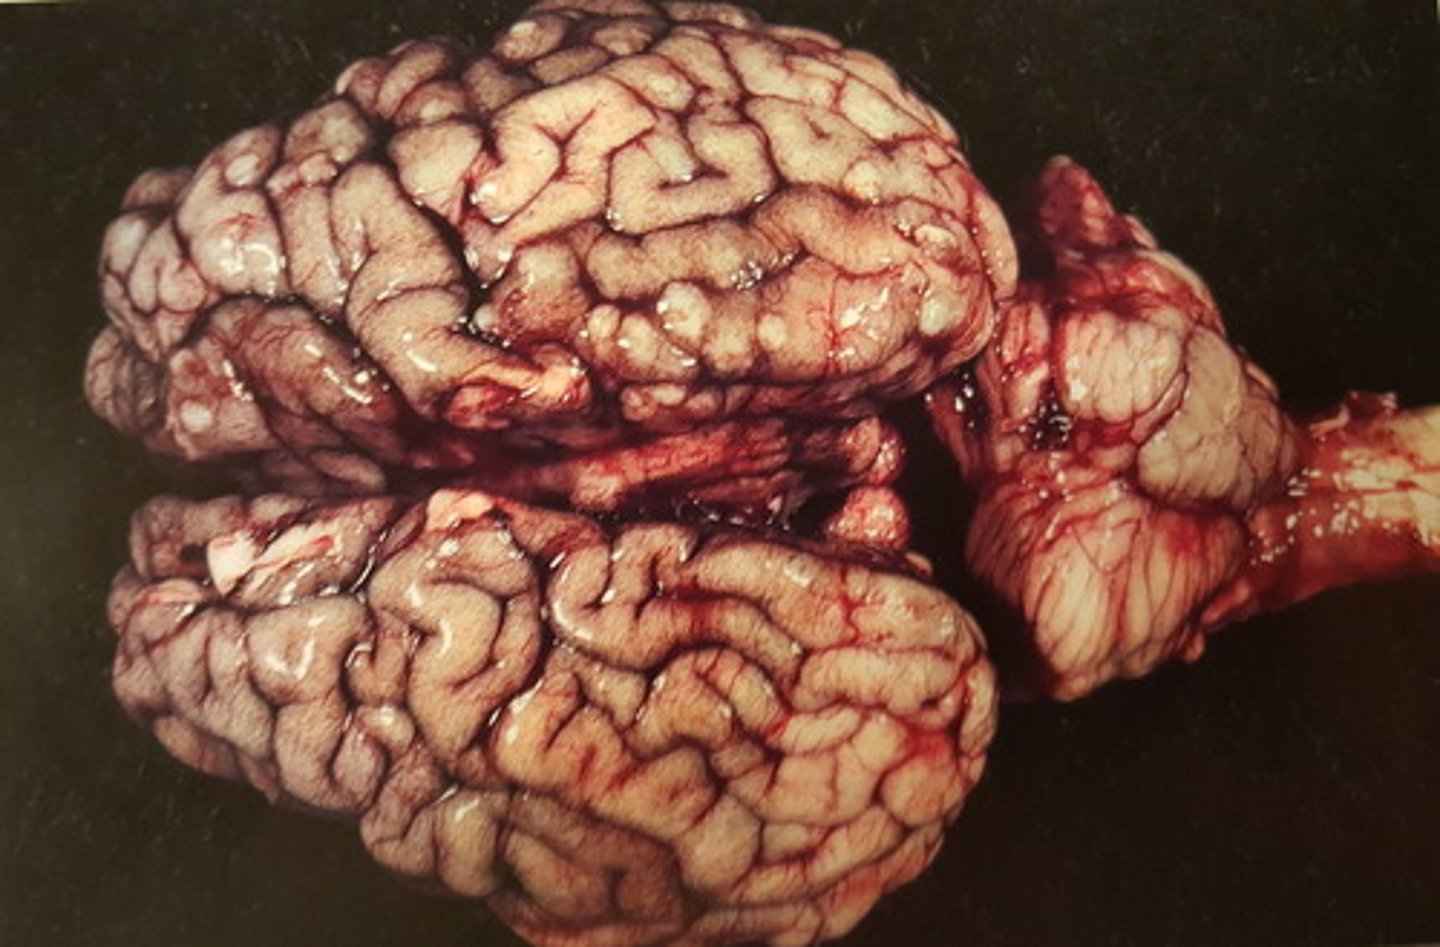

akut, diffus leptomeningitis.

Inflammation karakteriseret med ødem og hyperæmi

Hjerne fra okse. Patoanatomisk diagnose?